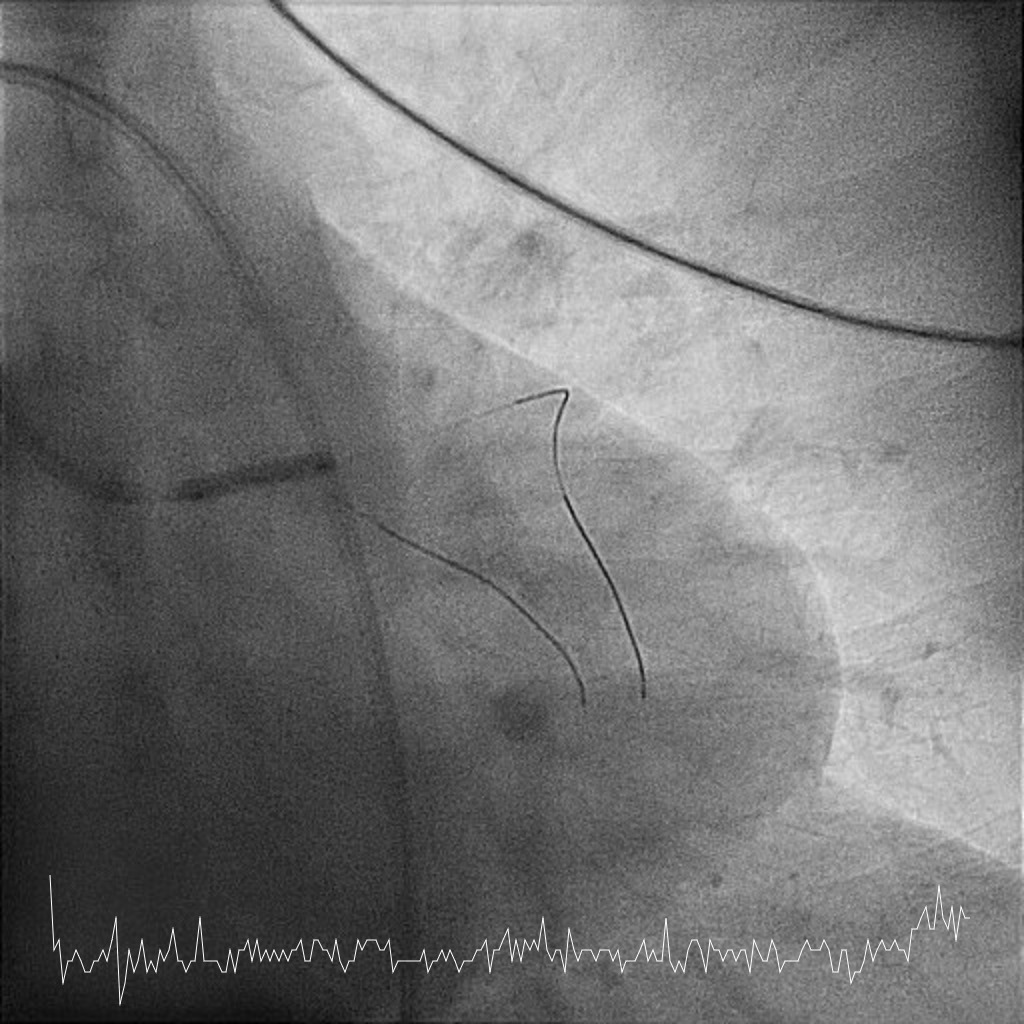

Femoral approach was chosen with a 7F sheath. A 7F JL4 guiding catheter was used for better support. JL4 was not coaxially engaged but positioned close to the ostial LM. Sion Blue ES was wired into LAD from the aortic cusp. A BMW wire was wired into LCx to provide additional support and as a safety wire in case of plaque shift into ostial LCx. Ostial LM was predilated with 3.0/10mm NC balloon at 12ATM which was delivered via Sion Blue ES with the guide and wire floating in the aorta. IVUS after predilatation revealed an ostial LM MLA 5.28mm2 with vessel size 4.0mm. Proximal LAD measured 3.0mm in size and exhibited fibrotic plaque with 70% plaque burden. Both ostial LM and proximal LAD were predilated with 3.0/15mm NC balloon delivered using the floating guide and Sion Blue ES. A 3.0/33mm DES was delivered and deployed with similar technique into proximal LAD using multiple projections for precise positioning to ensure proximal stent edge protrusion of 1-2mm into the aorta. POT of LM and ostial flare were performed using 3.75/15mm NC balloon. Proximal LAD was postdilated with 3.0/15mm NC balloon. IVUS confirmed a well-opposed stent without stent edge dissection. The final ostial LM MSA was 9.7mm2, with stent protrusion (1.7mm) into the aorta (less than one quadrant). The entire ostial LM was covered with stent struts.